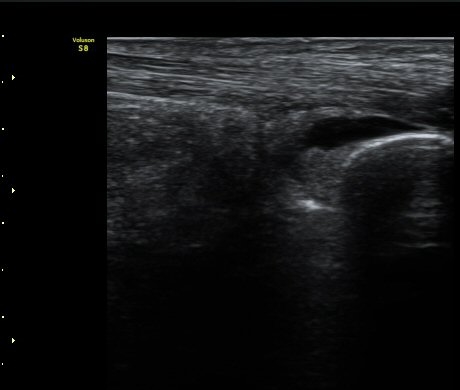

ÃÊÀ½ÆÄ °Ë»ç ÀÌų·¹½º ÈûÁÙ Á¾´Ü¸é°Ë»ç¿¡¼ ¾ÆÅ³·¹½º ÈûÁÙ ½ÉºÎ, Á¾°ñ»À ±ÙÀ§ºÎ¿¡ Ȱ¾×¸· Áõ½Ä°ú

¼ö¾×Àú·ù°¡ °üÂûµÇ°í(±×¸² 1) °ÇÃø°ú ºñ±³Çϸé Â÷À̰¡ ¶Ñ·È´Ù´Ù(±×¸² 2).